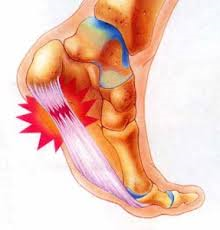

La fasciite plantaire (ou aponévrosite plantaire) désigne l'inflammation du fascia plantaire (voir les causes plus bas). Ce phénomène inflammatoire résulte de micro-traumatismes au point de jonction de cette membrane avec le talon, lorsque le fascia plantaire est trop sollicité (surcharge). Lorsque l'inflammation perdure et devient chronique, un processus de guérison peut s'enclencher spontanément : des cellules osseuses se forment alors pour soulager le fascia plantaire de la surcharge excessive. Une petite épine osseuse horizontale, qui pousse dans le sens de la marche, apparaît. Sa présence est mise en évidence par un simple l' examen radiologique.

Les principales manifestation sont les douleurs localisée du talon, généralement unilatérale), donnant l'impression de « marcher sur un clou ». Elles se manifestent surtout le matin, au lever et peuvent également faire suite à la pratique d'activités sportives.